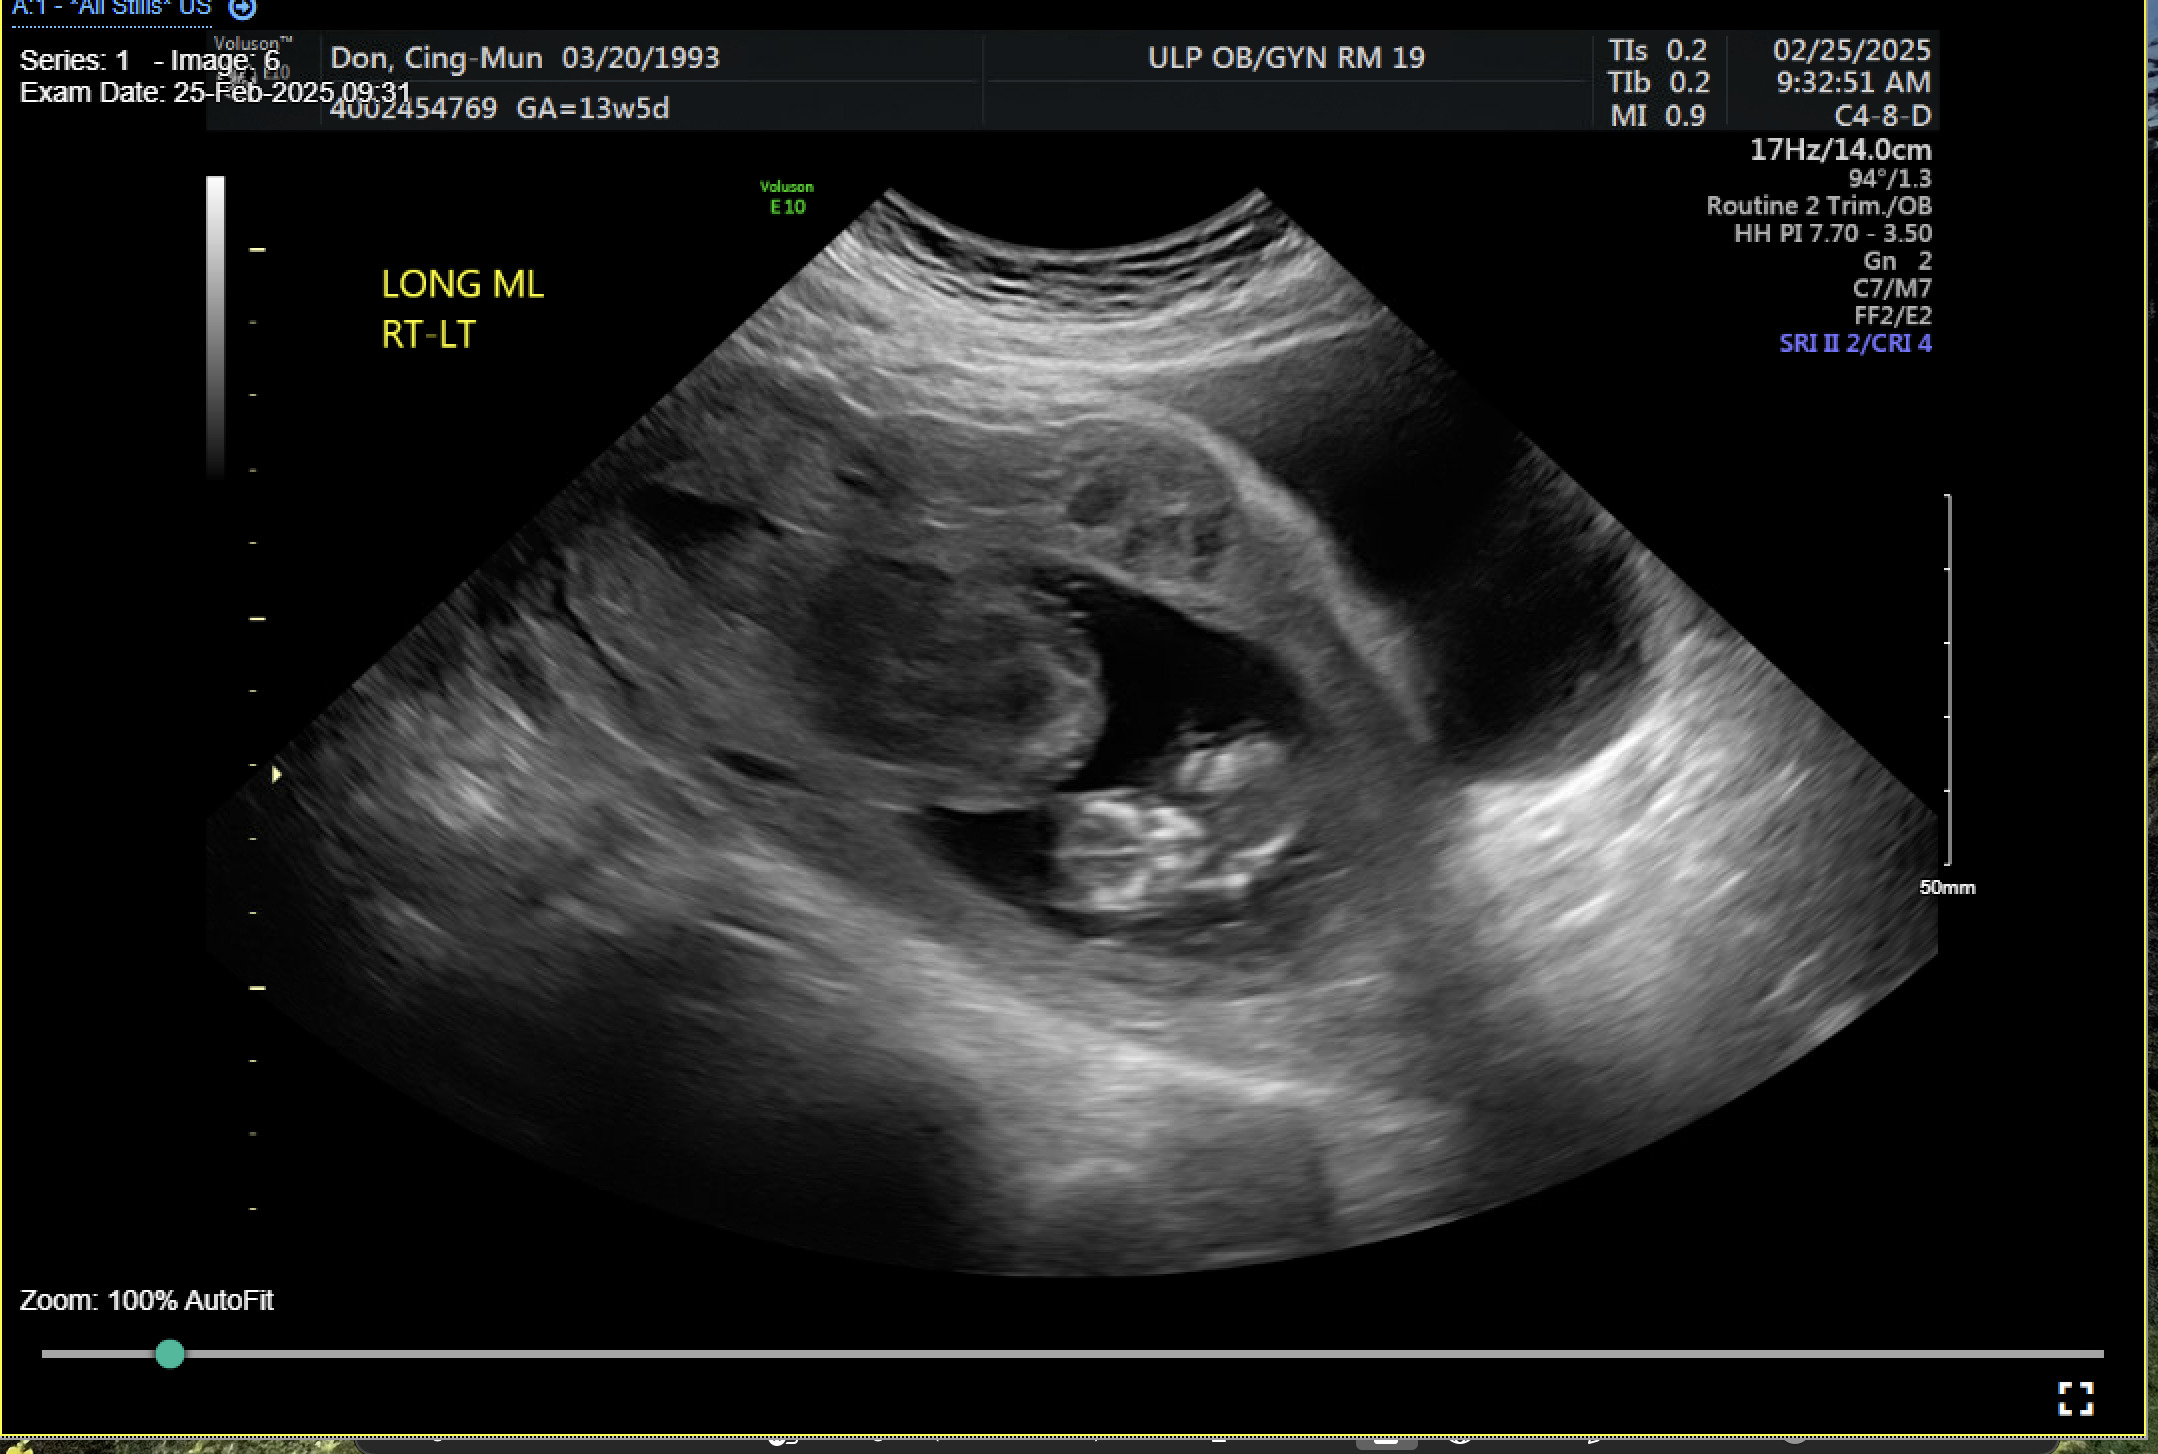

On admission for planned D&C, consents for laminaria placement, suction dilation and curettage under ultrasound guidance, possible uterine artery embolization, and possible hysterectomy were discussed and signed. The patient then underwent successful placement of a large and a medium-sized laminaria without complication. She subsequently underwent suction D&C with ultrasound guidance (Figure 3). Despite the prophylactic placement of 400 micrograms of rectal misoprostol and the administration of 20 units of Pitocin in IV fluids at the start of the case, the patient experienced significant hemorrhage during the procedure with an estimated blood loss of 1500 mL. Intraoperative findings raised concern for uterine rupture (Figure 4). A Foley balloon inflated with 30cc of saline was placed for attempted intrauterine tamponade (Figure 5), and a brisk blood loss of 500 mL immediately filled the foley catheter bag. Vaginal packing and intramuscular methergine were given as additional attempts to control the bleeding, but the patient’s hemodynamic status rapidly deteriorated. This necessitated volume resuscitation and transfusion of two units of packed red blood cells. An emergent exploratory laparotomy was then performed to identify the source of the bleeding with preparedness to repair any defects or perform a hysterectomy to prevent exsanguination. A thorough survey of the uterus, adnexa, and adjacent pelvic structures revealed no overt source of bleeding, uterine rupture, or organ invasion. The uterine and bladder serosa were intact. No hemoperitoneum was found. Further inspection revealed no additional blood loss beyond the 500 mL noted in the foley bag. Blood loss was ppropriately corrected for, and the patient became hemodynamically stable. The abdomen was closed, and the patient was transferred to interventional radiology for uterine artery embolization, prevented additional bloodloss. Following embolization, the patient was noted to be stable and extubated without issue.